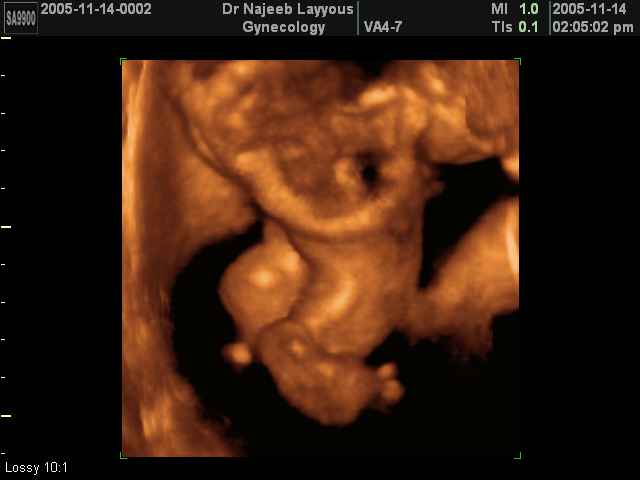

- لقطات فيديو للجنين بجهاز الموجات فوق صوتية رباعي الأبعاد

- صور لتصرفات الجنين داخل الرحم